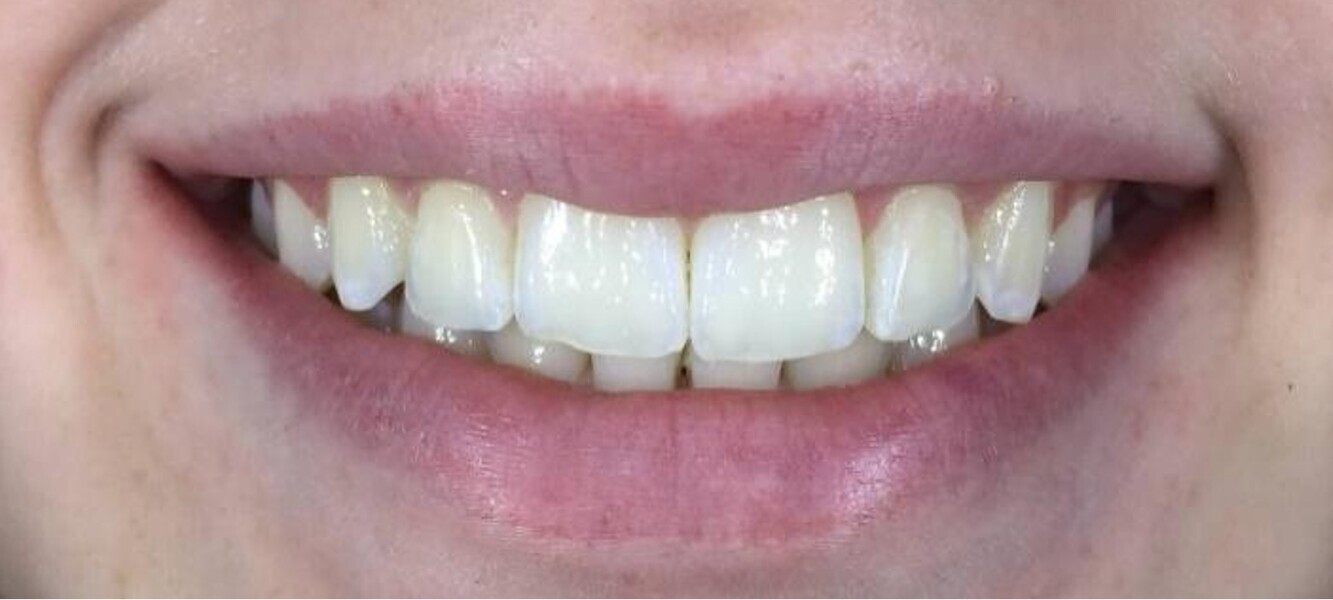

Fig. 12: Close-up view after soft-tissue recontouring, direct restoration and whitening.

Fig. 3: Close-up view of the patient’s smile.

peri-oral considerations; and

After six months of weekly changeover of aligners (25 out of 33 aligners in the maxillary arch and 25 out of 25 aligners in the mandibular arch and no refinement) and achieving adequate intrusion of the six maxillary anterior teeth, the pre-restorative segment of the treatment was complete (Figs. 5 & 6). The next phase was a digitally planned soft-tissue recontouring of the labial tissue of the six maxillary anterior teeth. For this purpose, a digital surgical guide was made by our laboratory at AORTA using our PRO 4K printer (Asiga; Figs. 7–10). This was followed by in-chair tooth whitening and then composite augmentation of the incisal edges of teeth #13–23 (Figs. 11 & 12). The patient was then placed into retention with Zendura FLX thermoplastic retainers (Bay Materials) based on resin 3D-printed models produced by our PRO 4K printer, providing accuracy and superior fit as observed by the patient. The retainers and models were all made by our dental laboratory at AORTA.